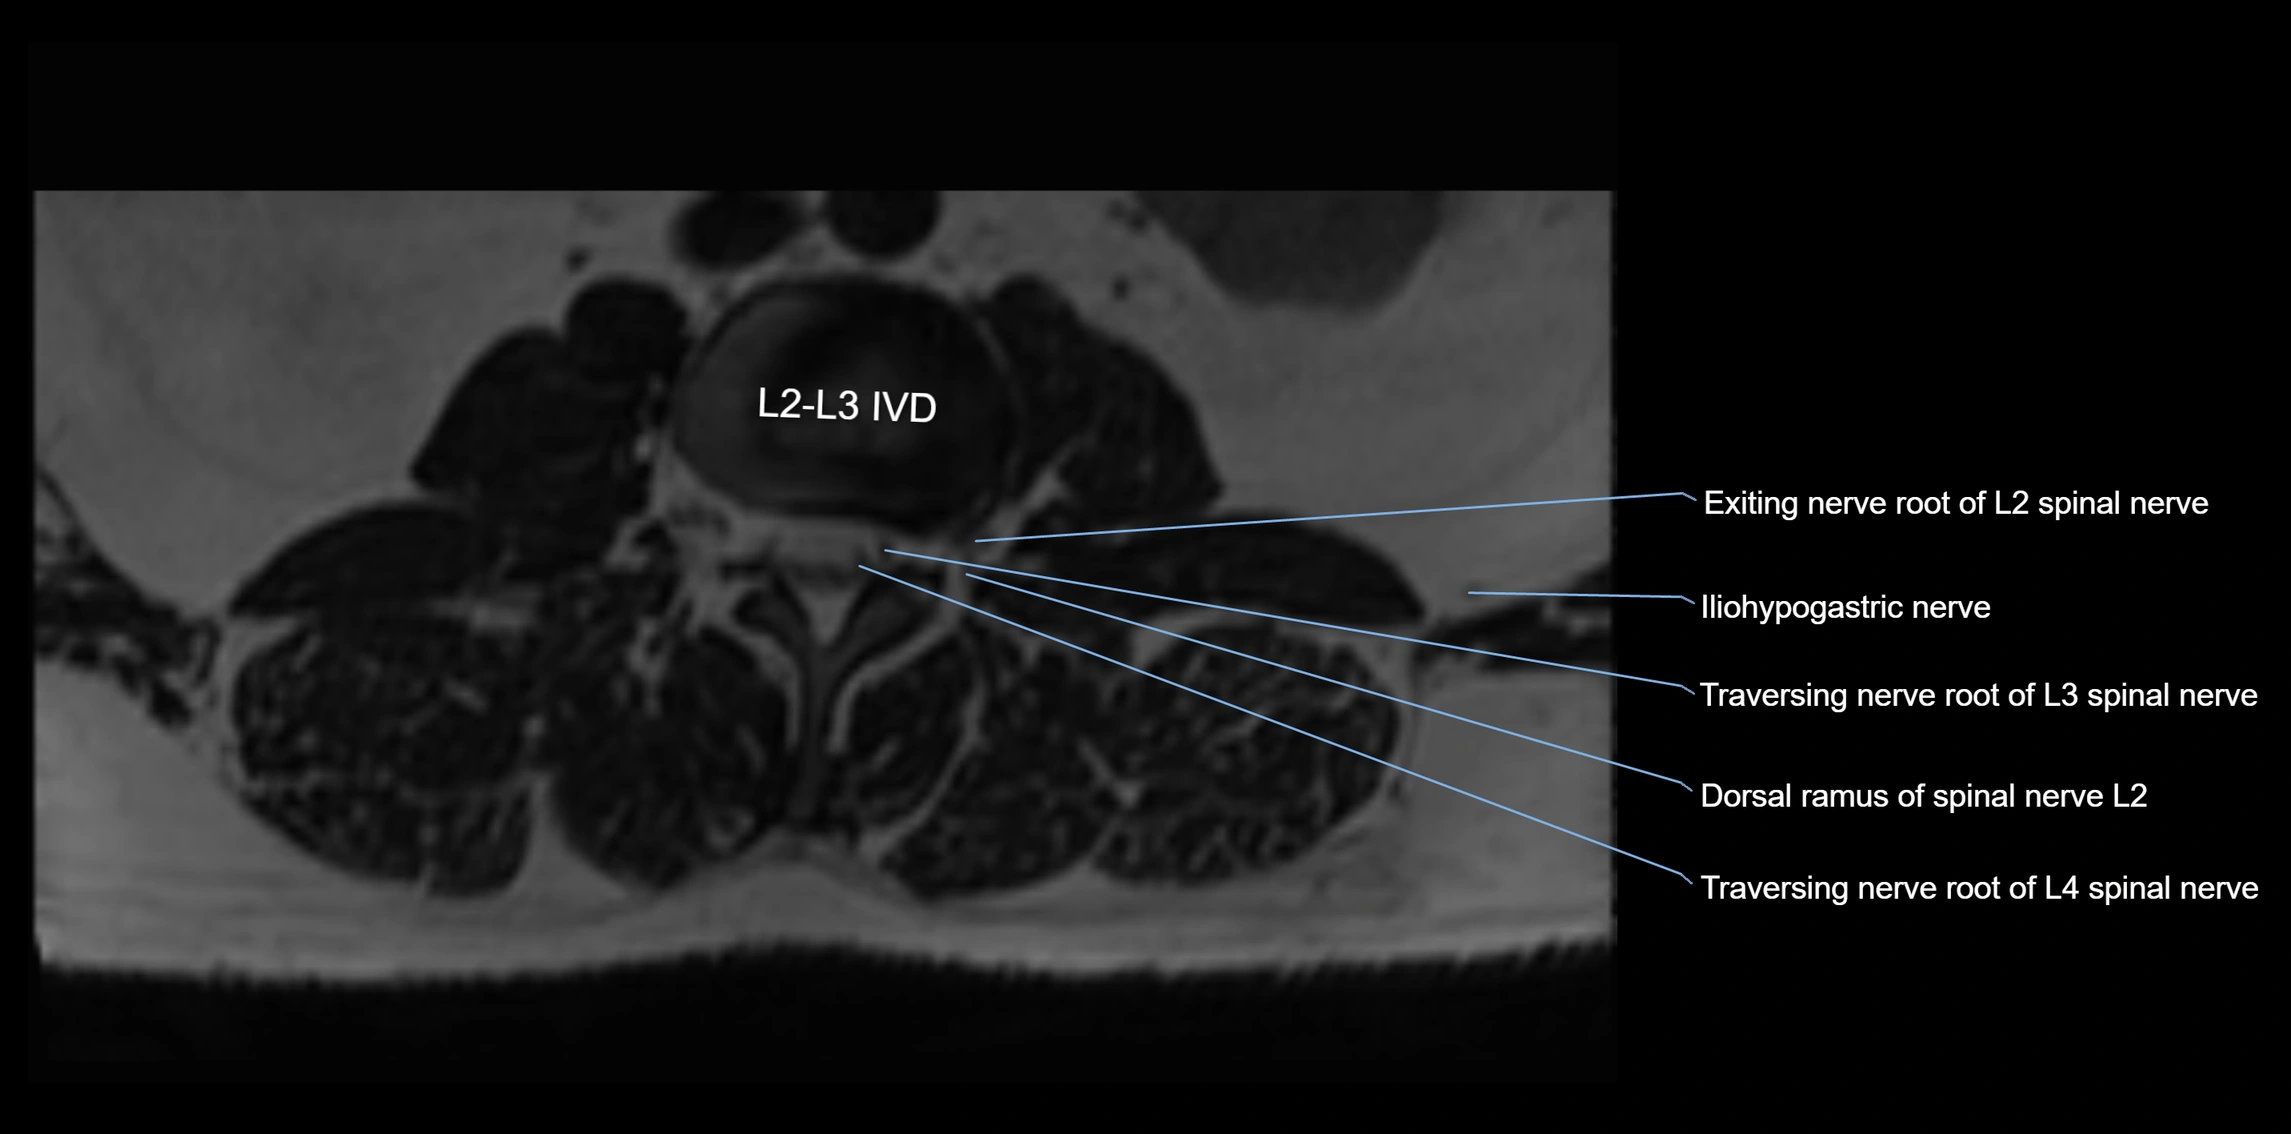

MRI Appearance

T1-weighted images:

• Nerve appears as a very thin low-to-intermediate signal intensity structure

• Surrounded by bright fat, aiding visualization

T2-weighted images:

• Nerve shows intermediate to mildly hyperintense signal compared to muscle

• Pathological involvement appears brighter

STIR (Short Tau Inversion Recovery):

• Normal nerve appears dark

• Inflamed or entrapped nerve appears bright hyperintense

T1 Fat-Sat Post-Contrast:

• Normal nerve enhances minimally

• Pathologic nerve (neuritis, entrapment, tumor infiltration) shows focal or diffuse enhancement

3D T2 SPACE / CISS:

• Nerve appears intermediate to mildly hyperintense compared to muscle

• Surrounded by bright fat or CSF, improving visualization

• Best sequence for mapping small pelvic nerves such as the anococcygeal